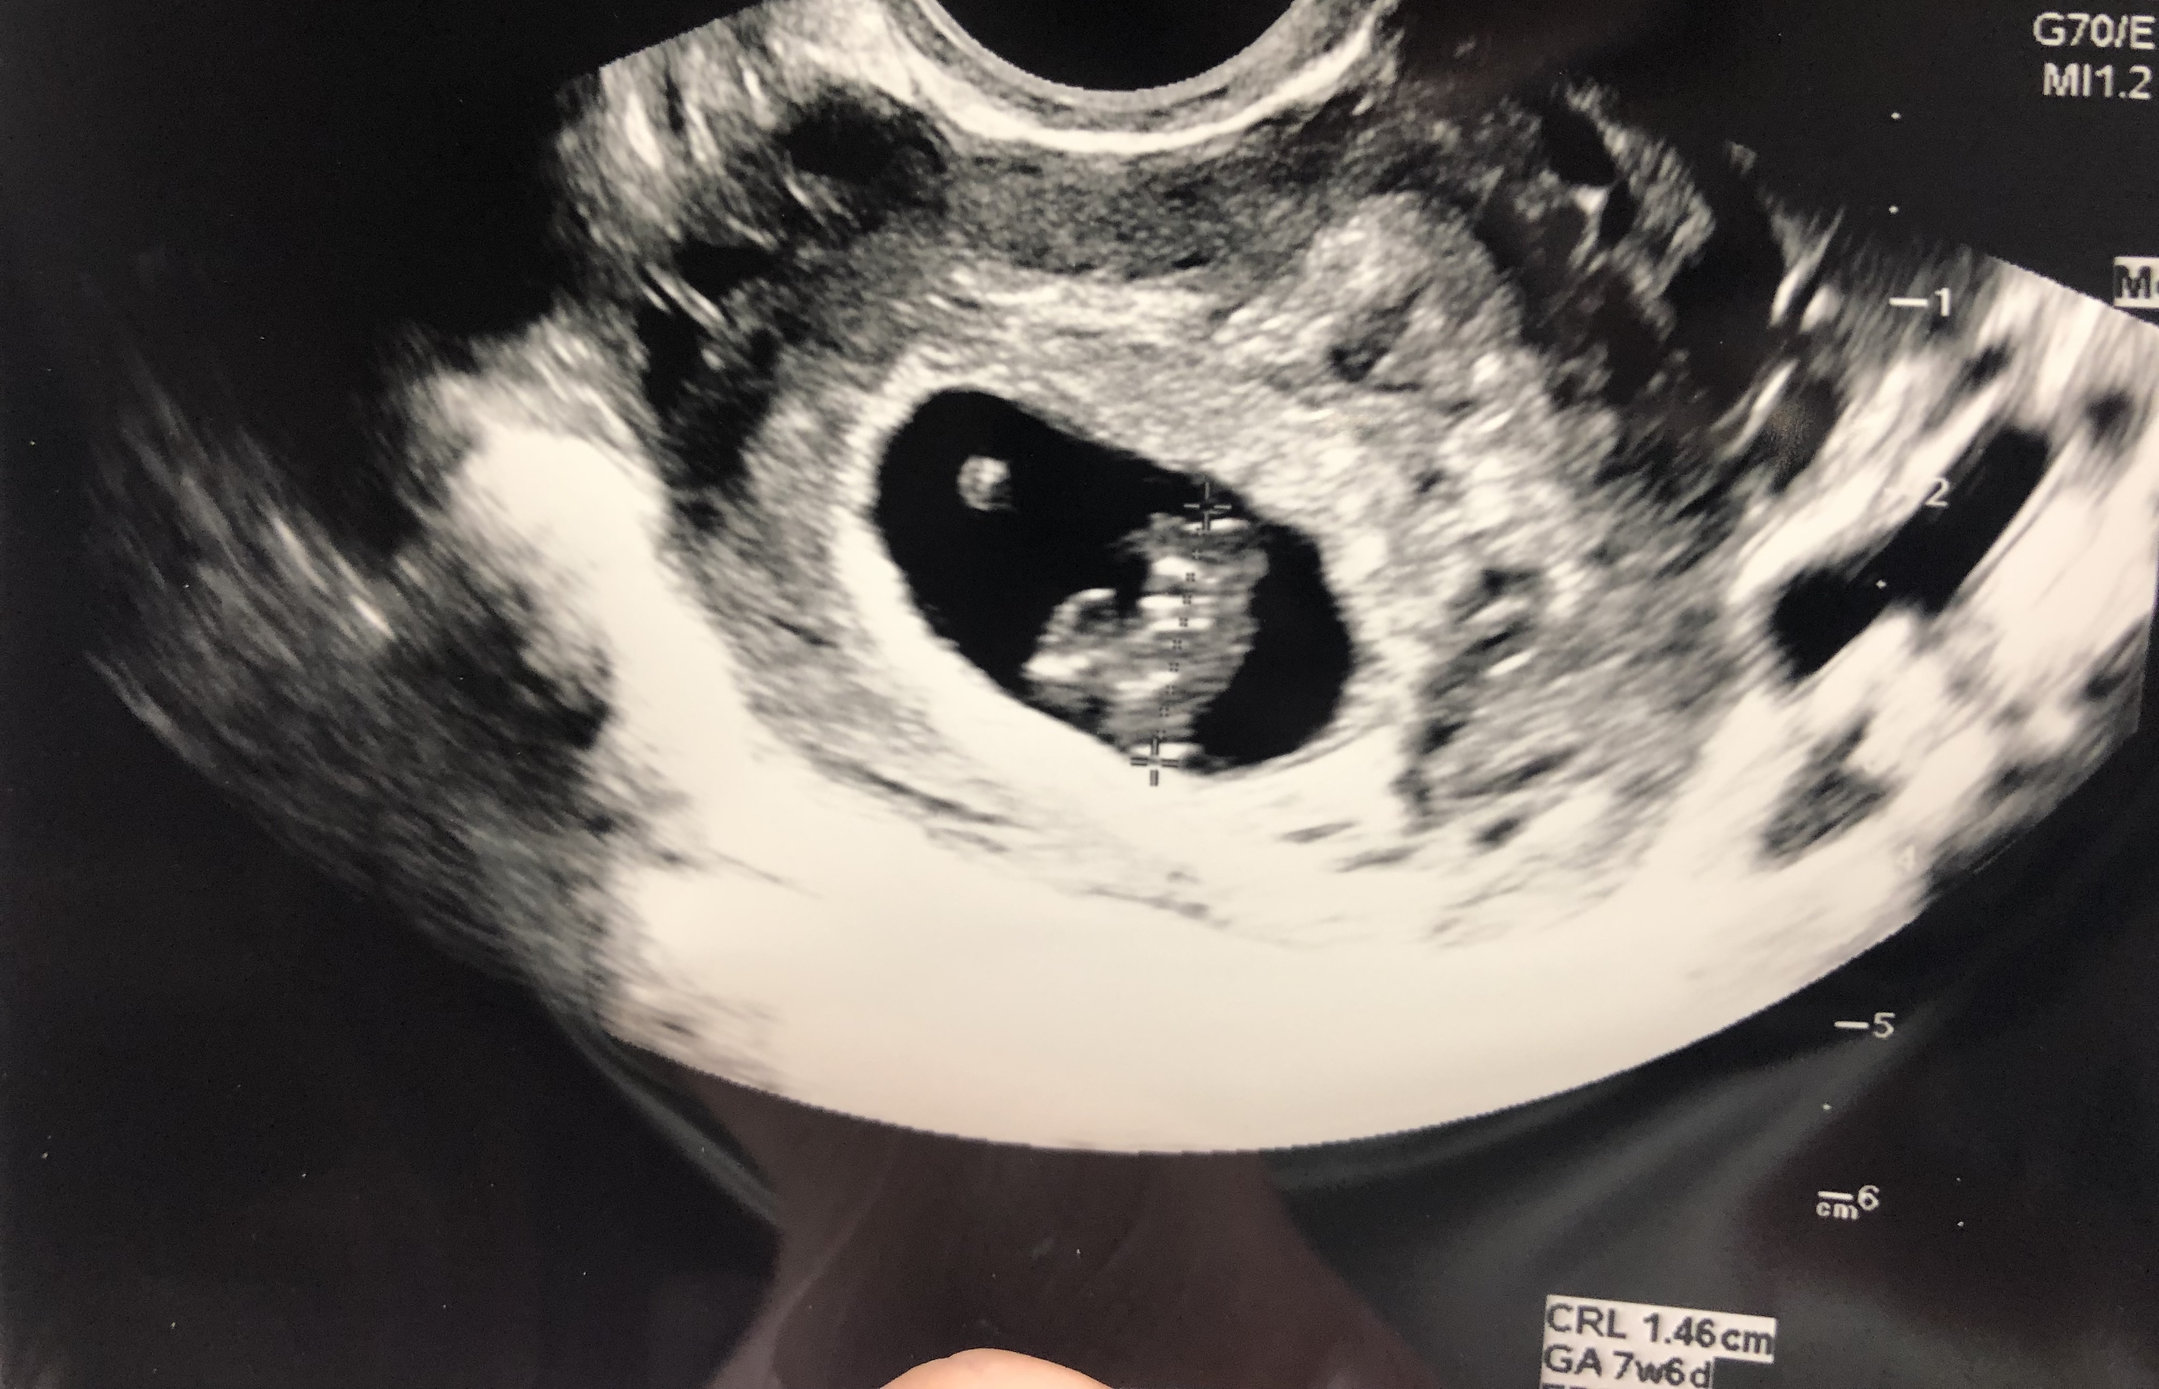

Measuring exactly what we thought it should be (7 weeks 6 days) and heartrate of 157 bpm. Definitely cried some happy tears seeing our little gummy bear. ❤ With my first pregnancy I MCd before we even got an ultrasound, so this was really my first experience seeing a baby on the monitor.